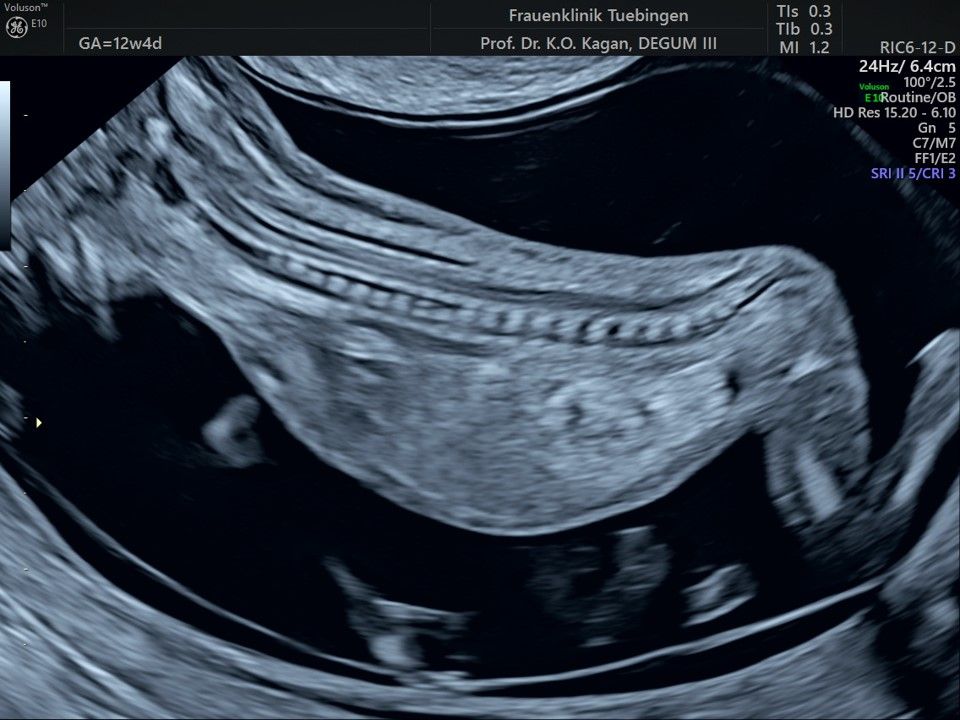

Im Rahmen des Ersttrimester-Screenings untersuchen wir die Organe des Feten mittels Ultraschall. Dabei machen wir auch gerne ein Bild für Sie.

Obwohl der Fet zu diesem Zeitpunkt erst zwischen 5 und 8cm groß ist, lassen sich bereits etwa die Hälfte aller schwerwiegenden Fehlbildungen erkennen bzw. ausschließen. Sollten wir eine Auffälligkeit sehen, werden wir mit Ihnen den Befund und das weitere Vorgehen ausführlich besprechen.

Bauchwanddefekt